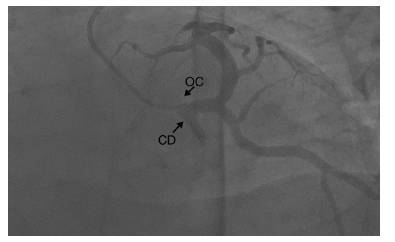

Figura 2 Arteriografía coronaria, se muestra origen común de arteria coronaria con trayecto interarterial. OC: origen común; CD: coronaria derecha.

Figura 3 Arteriografía coronaria, se muestra origen común de arteria coronaria con trayecto interarterial. OC: origen común; CD: coronaria derecha.